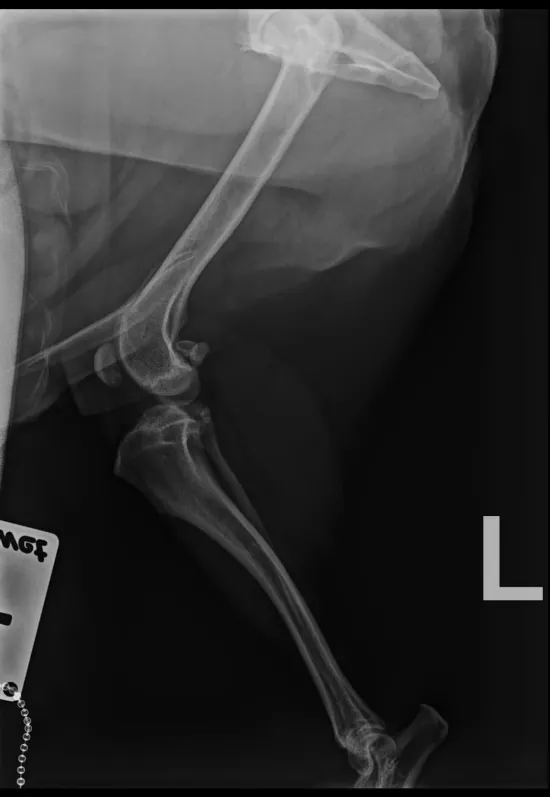

Niedawno zdiagnozowano u niego poważne problemy ortopedyczne. Badanie RTG wykazało:

- silne zmiany zwyrodnieniowe i przebudowę główki kości udowej w lewym stawie biodrowym,

- zmiany zapalne w prawym stawie kolanowym (podejrzenie tzw. myszy stawowej).

W pierwszej kolejności konieczna jest operacja lewego biodra - dekapitacja główki kości udowej.